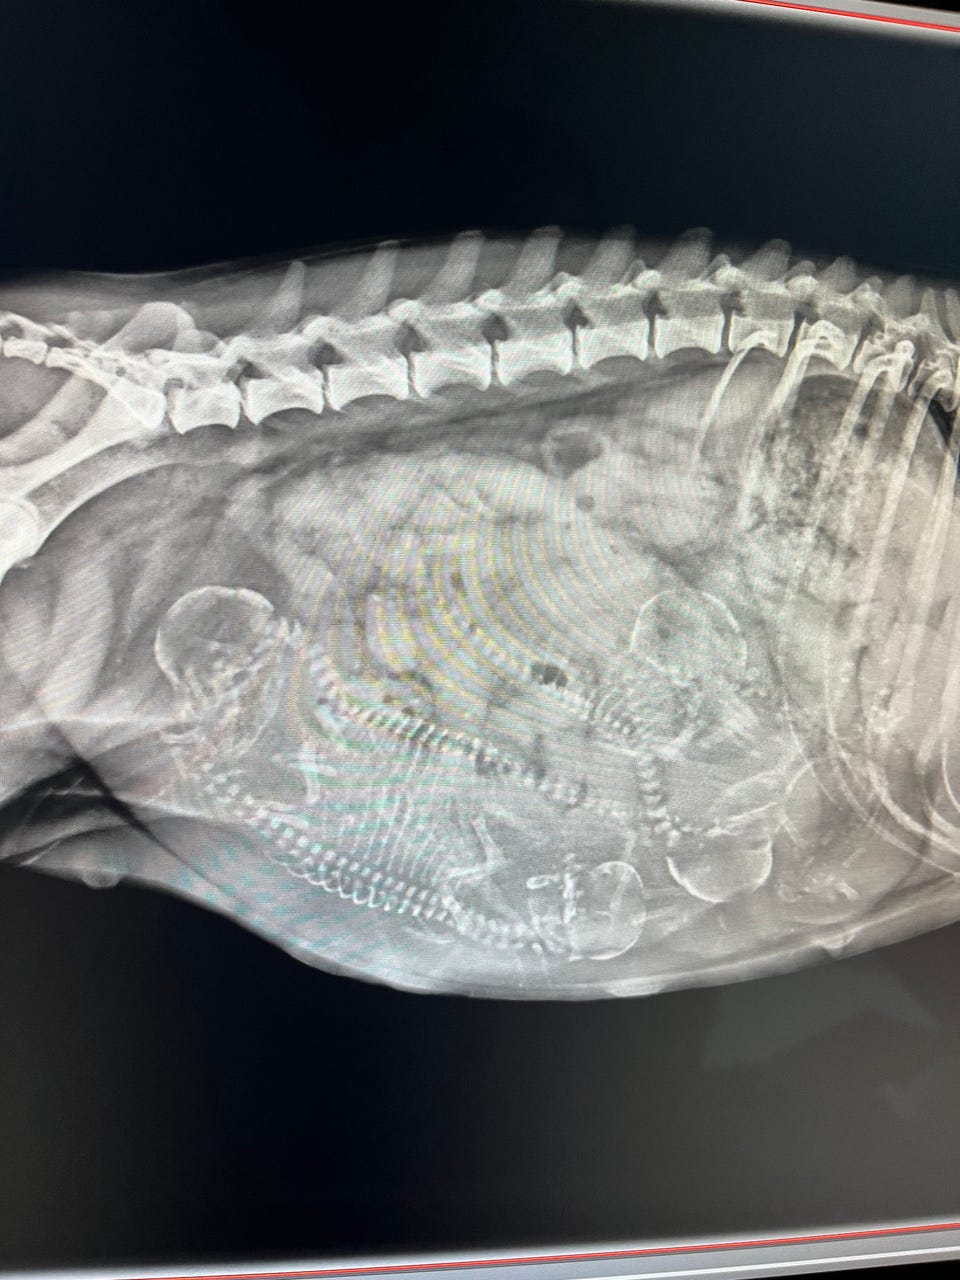

Vi forventer 4 søde hvalpe omkring start april.

Jessie er en sød chihuahua blandning og vejer omkring 4-5 kg

Blackie er bichon havanais (uden tavle) og vejer 6,05 kg.

Jessie har selvfølgelig fået det basale sundhedstjek og er sund og rask.

Han er også blevet testet for patella med resultat 0/0.